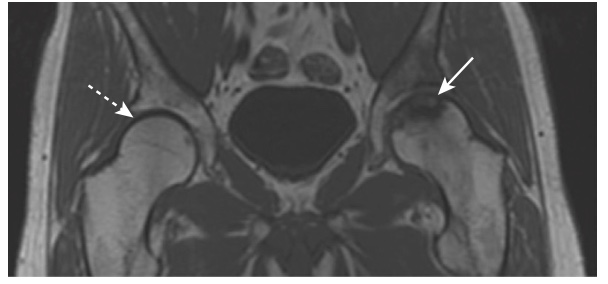

- Trên phim X quang thông thường, vùng hoại tử vô mạch xuất hiện đậm đặc hơn vùng xương xung quanh. Trên MRI, thường có sự giảm tín hiệu so với bình thường (cao) do tủy mỡ (Hình-6).